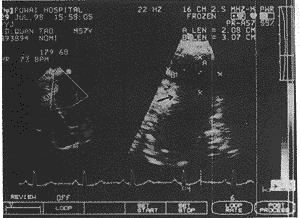

心尖呈局限性瘤样膨出,瘤颈部小于扩张的瘤体和左室径

图1 超声心动图心尖四腔切面:收缩期

可见心尖下部瘤样膨出,瘤的颈部室间隔侧心肌异常突起,一方面形成狭小口径,另一方面类似假性室壁瘤的断端